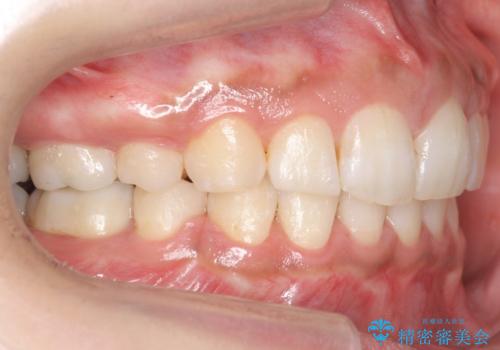

- 前歯を下げたいと来院。

初めは、上だけ抜歯しましたが、もう少し口元を下げたいとのことで追加で下顎を抜歯しました。

年齢の割に歯が動きにくかったこともあり、また、追加で抜歯して結果として時間がかかってしまいました。口元が大きく下がり、結果には満足していただけました。